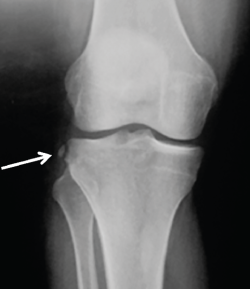

Figura 2. Radiografía anteroposterior de una rodilla derecha, donde puede apreciarse una fractura de Segond (flecha blanca).

- Radiografía (Rx): la imagen radiológica más característica que se relaciona con la lesión del LAL es la fractura de Segond, aunque esta solo está presente en un 1,25% de los pacientes con lesión de LCA(34)(Figura 2).

- Fractura de Segond(48): aunque existe algún trabajo que indica que la fractura de Segond no es un factor de riesgo para la rerrotura de la reconstrucción del LCA(56), los principales grupos aconsejan la reconstrucción del complejo AL cuando esta está presente(42), ya que es sabido que tanto la capa capsuloósea de la banda iliotibial como el LAL(57), así como una expansión de la fascia de la cabeza corta del bíceps femoral(58), están insertados en este punto(41).